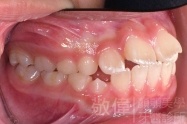

矯正前-右   矯正前-正   矯正前-左

矯正後-右   矯正後-正   矯正後-左

上顎暴牙且牙齒極度混亂,經由矯正之後,臉型大幅度改善,牙齒的排列更加的整齊健康。相較於之前眼神充滿精神,自信心展現無遺。